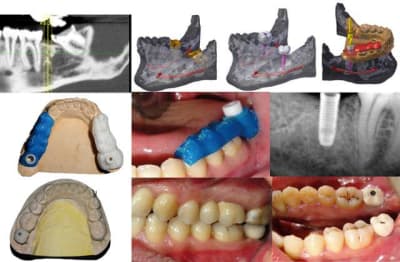

> voila comme promis une vidéo planif et guide entièrement faite avec blender sans utiliser meshlab

> Collage du platre

> Guide

> Test des différents forets

toujours avec mon nouveau jouet, je n'avais jamais testé mais cela fonctionne parfaitement bien

plus besoin de faire couler le plâtre par le labo!!!

un scan ou un cone beam de l'empreinte suffit

très simple ensuite de préparer une provisoire

bonsoir tout le monde

on en est a faire quelques guides et des modeles biologiques, merci a Be Open Plan, le dernier a été imprimé chez I-materialise en poly1500 matériaux biocompatible en belgique, je posterai le cas une fois terminé. en attendant on s'amuse ;)